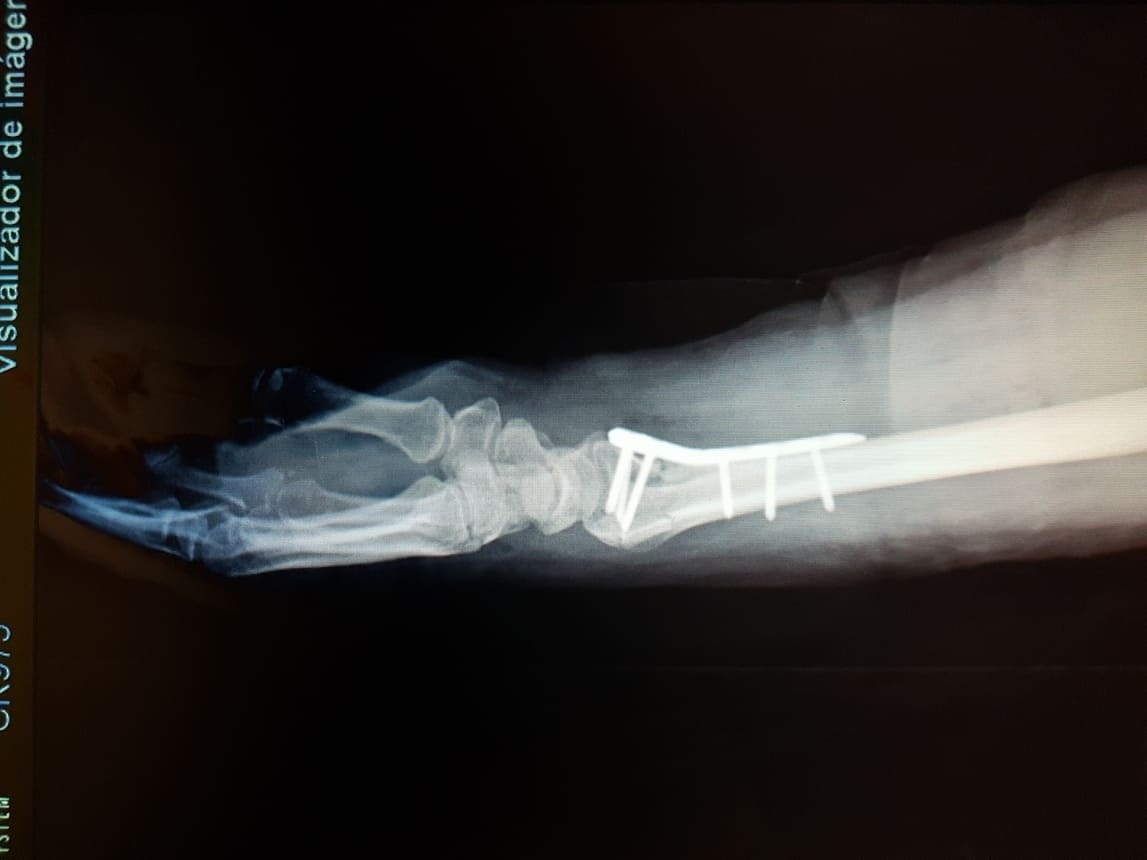

TRATAMIENTO DE FRACTURAS - GALERÍA DE IMÁGENES

Fractura de radio distal